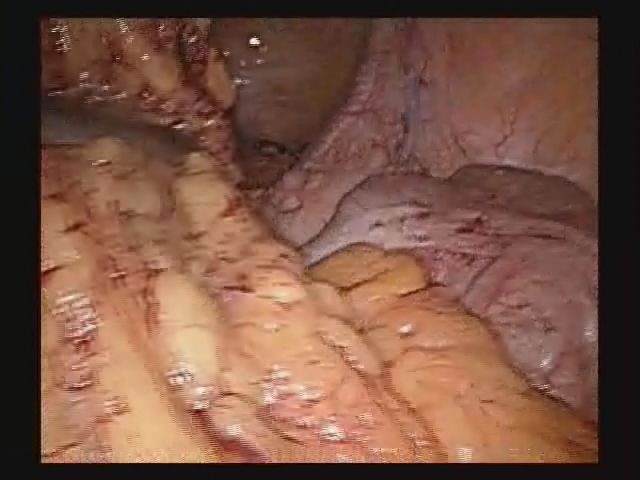

Robotic Repair of Rectovesic..

Robotic Repair of Rectovesic..

Rene Sotelo, MD; Robert J. De Andrade, MD; Oswaldo Carmona, MD; Juan C. Astigueta, MD; Alejandro Vel / CINE-MED